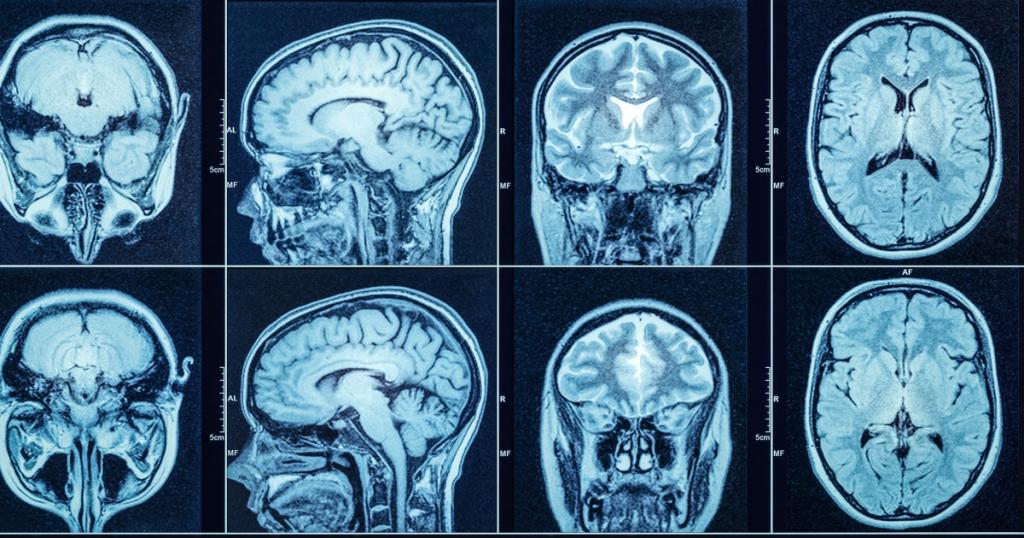

Durch die Untersuchung von Hirnflüssigkeit, viraler Persistenz und MRTs verbessern wir unser Verständnis für das “Wie” und “Warum” dieser verheerenden Krankheit.

Die Bildgebung des Gehirns vor und nach #COVID zeigt Veränderungen.

In der inzwischen berühmten UK Biobank vom 7. März 2022 @NatureMedicine Studie wurden bei 401 Personen, von denen die meisten eine leichte #COVID hatten und nicht ins Krankenhaus eingeliefert wurden, MRTs vor und nach der Infektion durchgeführt.

Im Vergleich zu 384 Kontrollpersonen, die nie an COVID erkrankt waren, ergaben sich verblüffende Ergebnisse.

Die Anomalien wurden vor allem im limbischen System und in den Geruchsbereichen festgestellt.

Die zweiten Scans wurden ~5 Monate nach COVID durchgeführt.

Die Patienten mit MRT-Veränderungen wiesen auch nach Ausschluss derjenigen, die im Krankenhaus waren, einen stärkeren kognitiven Rückgang auf.

Für unsere #Neurowissenschaftsjunkies hier die Ergebnisse der MRTs:

Größere Abnahme der Dicke der grauen Substanz und des Gewebekontrasts im orbitofrontalen Kortex, im parahippocampalen Gyrus und im olfaktorischen Kortex.

“VERRINGERUNG DER GESAMTGRÖSSE DES GEHIRNS”.